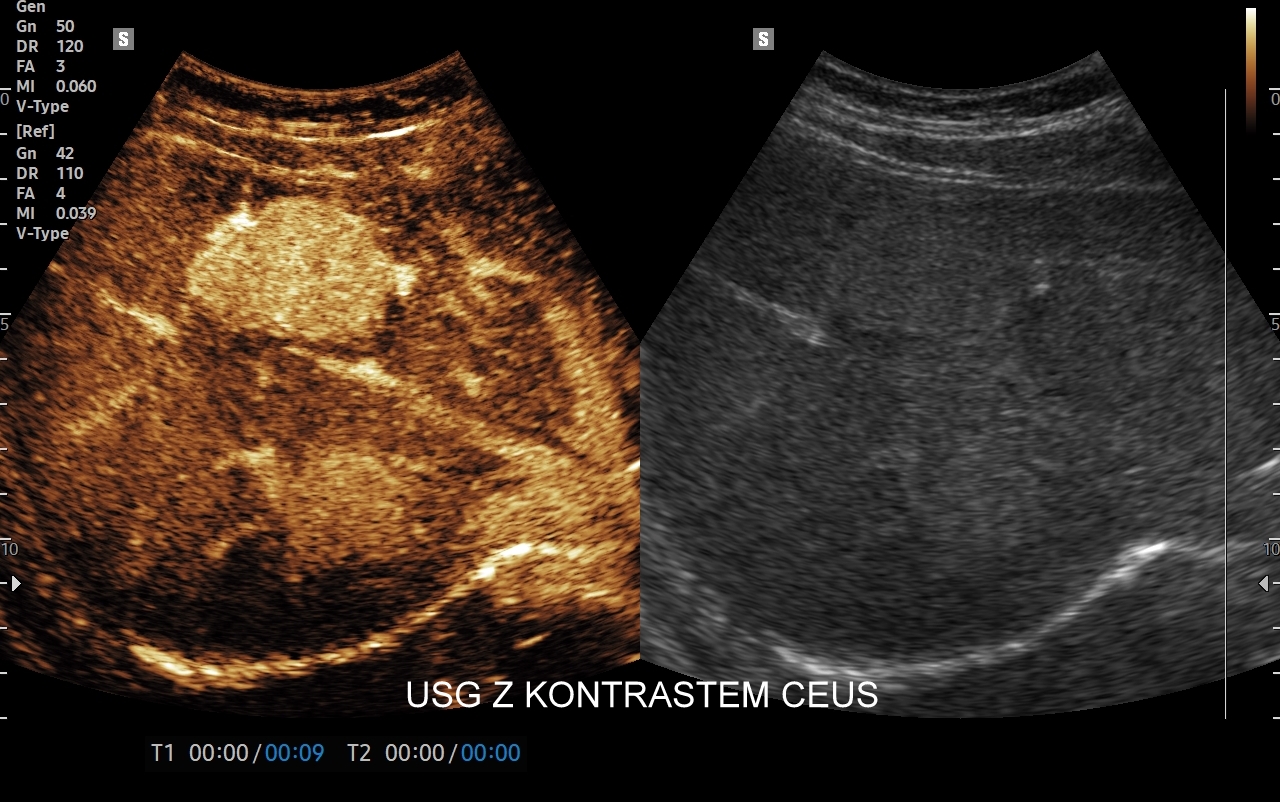

Badanie USG z kontrastem, z języka angielskiego CEUS (contrast enhanced ultrasound), jest badaniem ultrasonograficznym, podczas którego, zwykle dożylnie, podaje się specjalny kontrast w celu uwidocznienia struktur narządowych oraz tkanek, które niewystarczająco wyraźnie są widoczne lub charakteryzowane w klasycznym badaniu USG, a nawet w innych badaniach obrazowych jak tomografia komputerowa (TK) czy rezonans magnetyczny (MRI).

Strukturę kontrastu do USG stanowią mikropęcherzyki o wielkości <10 μm zbudowane z osłonki lipidowej, w której zamknięty jest neutralny gaz heksafluorek siarki (SF6). Mikropęcherzyki po podaniu dożylnym przedostają się mikrokrążenia narządów i są w nich wykrywane za pomocą obrazowania USG specjalnie do tego przystosowanym aparatem. Oprócz dożylnego podawania kontrastu, w przypadku niektórych wskazań, może być on także administrowany dopęcherzowo.

Badanie USG z kontrastem najczęściej wykorzystuje się do oceny zmian ogniskowych w wątrobie, potocznie nazywanych guzami wątroby, z których wiele ma na tyle specyficzny obraz mikrounaczynienia w obrazowaniu CEUS, że możliwe jest uniknięcie konieczności badania obciążającymi metodami TK lub MRI. Badanie CEUS w przeważającej większości pozwala odpowiedzieć, czy zmiana ogniskowa wątroby ma cechy złośliwe czy łagodne. Dodatkowo CEUS jest pomocny do wykrywania przerzutów do wątroby pochodzących z nowotworów w innej lokalizacji. W przypadku przerzutów o wielkości mniejszej niż 1 cm CEUS ma większą czułość aniżeli badanie TK.

CEUS jest badaniem w czasie rzeczywistym pozostającym pod kontrolą operatora, podczas którego możliwe jest wykonanie próby czynnościowej oraz natychmiastowe powtórzenie całego badania w razie konieczności. Możliwości takich nie dają ani TK ani MRI. Dodatkowo CEUS cechuje się o wiele większą rozdzielczością czasową w porównaniu do wspomnianych metod, co umożliwia uwidocznienie wczesnej fazy tętniczej unaczynienia podejrzanej onkologicznie zmiany ogniskowej w wątrobie i jej lepszą charakterystykę.